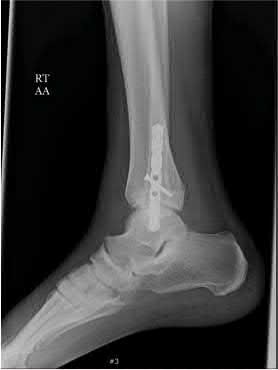

A 25-year-old male sustains an ankle fracture dislocation and undergoes open reduction and internal fixation. He returns to clinic five months following surgery complaining of continued ankle pain and instability with weight bearing. His immediate post-operative AP radiograph is seen in Figure A. Which of the following could have prevented this patient from developing persistent pain?

The patient presents with continued ankle pain and instability following open reduction and internal fixation. The radiograph in figure A demonstrates inadequate restoration of fibular length, likely leading to continued tibiotalar instability.